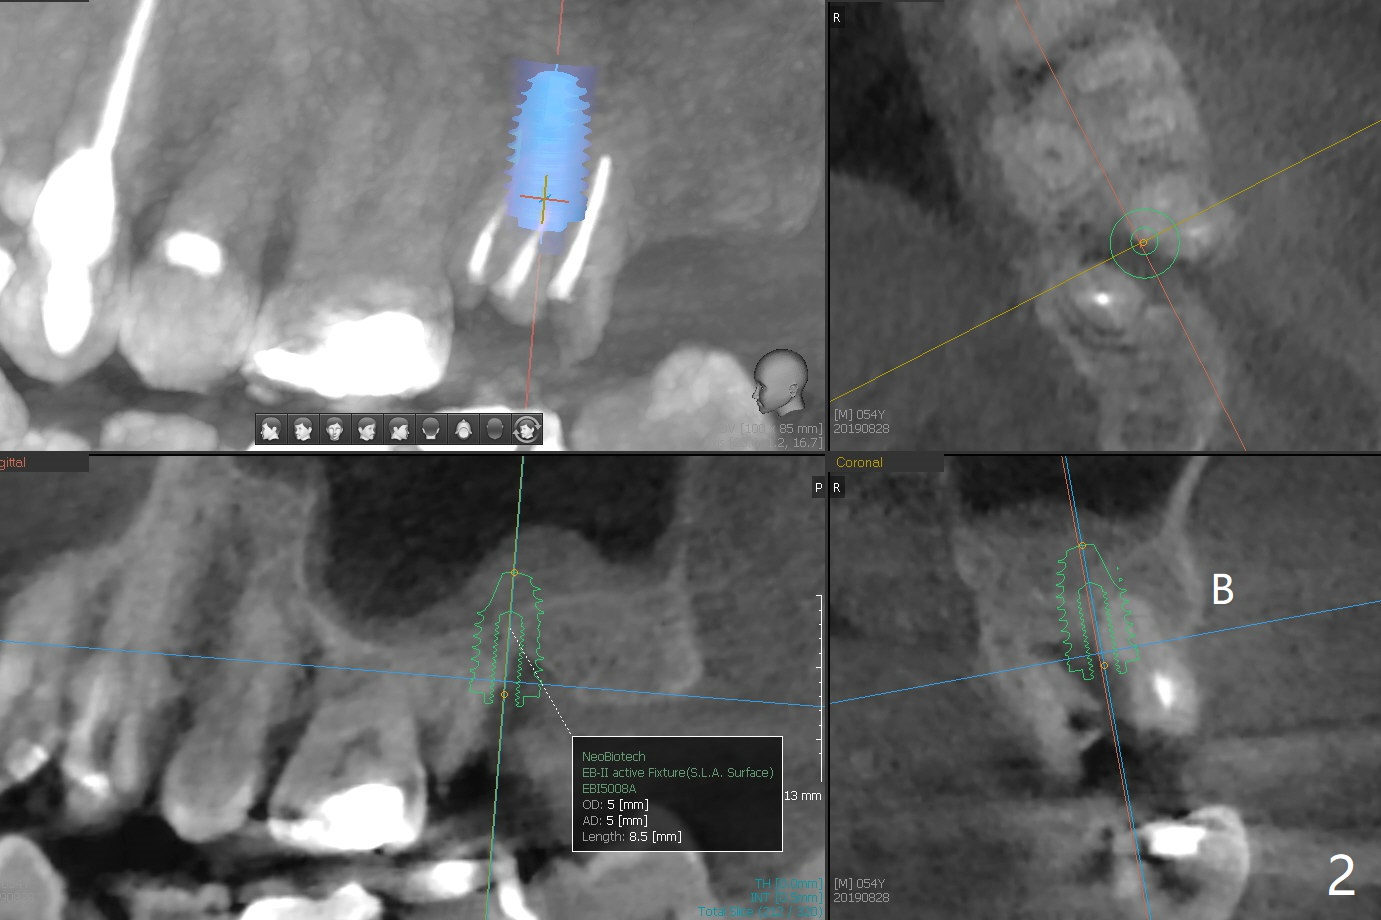

A 54-year-old man (smoker (3-4 cigarettes/day)) has two teeth that need to be replaced by implants (Fig.1). In order not to disturb the mucocele (Fig.1 *) above the tooth #15 to large degree, a short implant will be placed in the septum (not in the buccal socket (not disrupt the short buccal plate), Fig.2). Prepare PRFx1. Double check salvageability of the tooth #4. If needed, a 4.5x13 mm implant will be placed (Fig.3).